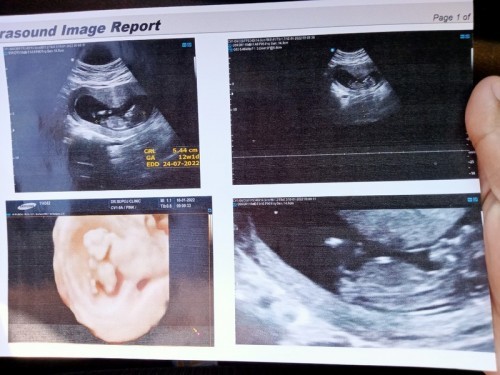

ขอดูภาพซาวด์ของแม่ๆบ้านอื่นหน่อยค่ะ บ้านนี้ 12w 1d จ้าา😄😄

12สัปดาห์จร้า น้องตัวจิ๋ว #ทีมกันยา